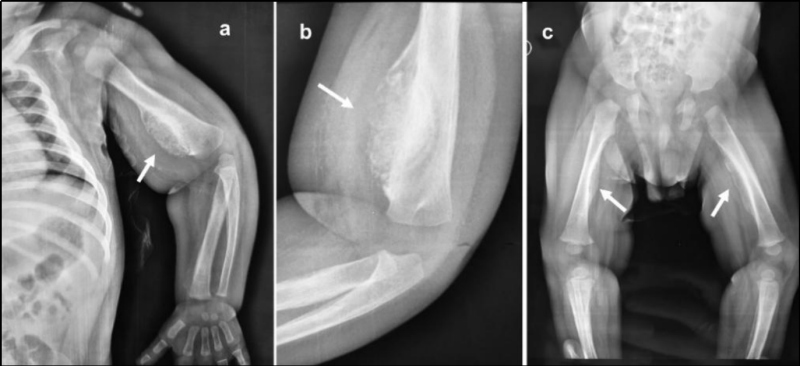

Paciente de 7 meses, sin antecedentes patológicos, traído a la consulta por dolor a la movilización del miembro superior izquierdo, de 5 días de evolución. Madre de oficio boxeadora profesional. Al examen físico se evidencia tumoración local en miembro superior izquierdo, sin signos inflamatorios y con movilidad disminuida, sin otra alteración evidente. Se realizan radiografías de miembros superiores e inferiores que muestran lesiones óseas (Fig. 1), por lo que se decide su internación por sospecha inicial de maltrato infantil.

Debido al hallazgo de captación anómala a nivel mandibular se arribó a la presunción diagnóstica de EC, realizándose biopsia del húmero izquierdo que informó hueso reticular neoformado con reborde osteoblástico y médula fibrovascular sin atipia celular, cuadro histológico compatible con hiperostosis cortical infantil.